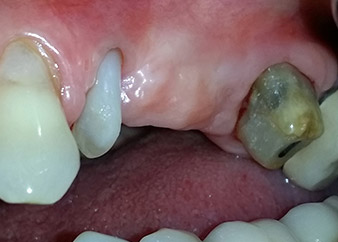

Un mois plus tard, le jour de l'intervention, la douleur et l'inflammation sur la dent 24 étaient minimes mais une mobilité de classe 2 de Miller était toujours observable. Après ouverture des lambeaux et nettoyage des tissus périapicaux et périradiculaires infectés, l'étendue du défaut osseux est devenue parfaitement visible (Figures 2 et 3).

À la racine de la dent, il manquait la totalité de l'os vestibulaire et distal. L'attache était essentiellement limitée à la racine palatine, venant ainsi confirmer le pronostic défavorable initial. La dent 27 présentait également une attache horizontale réduite et une raréfaction apicale minime (cf. Fig. 1), sans symptômes cliniques.